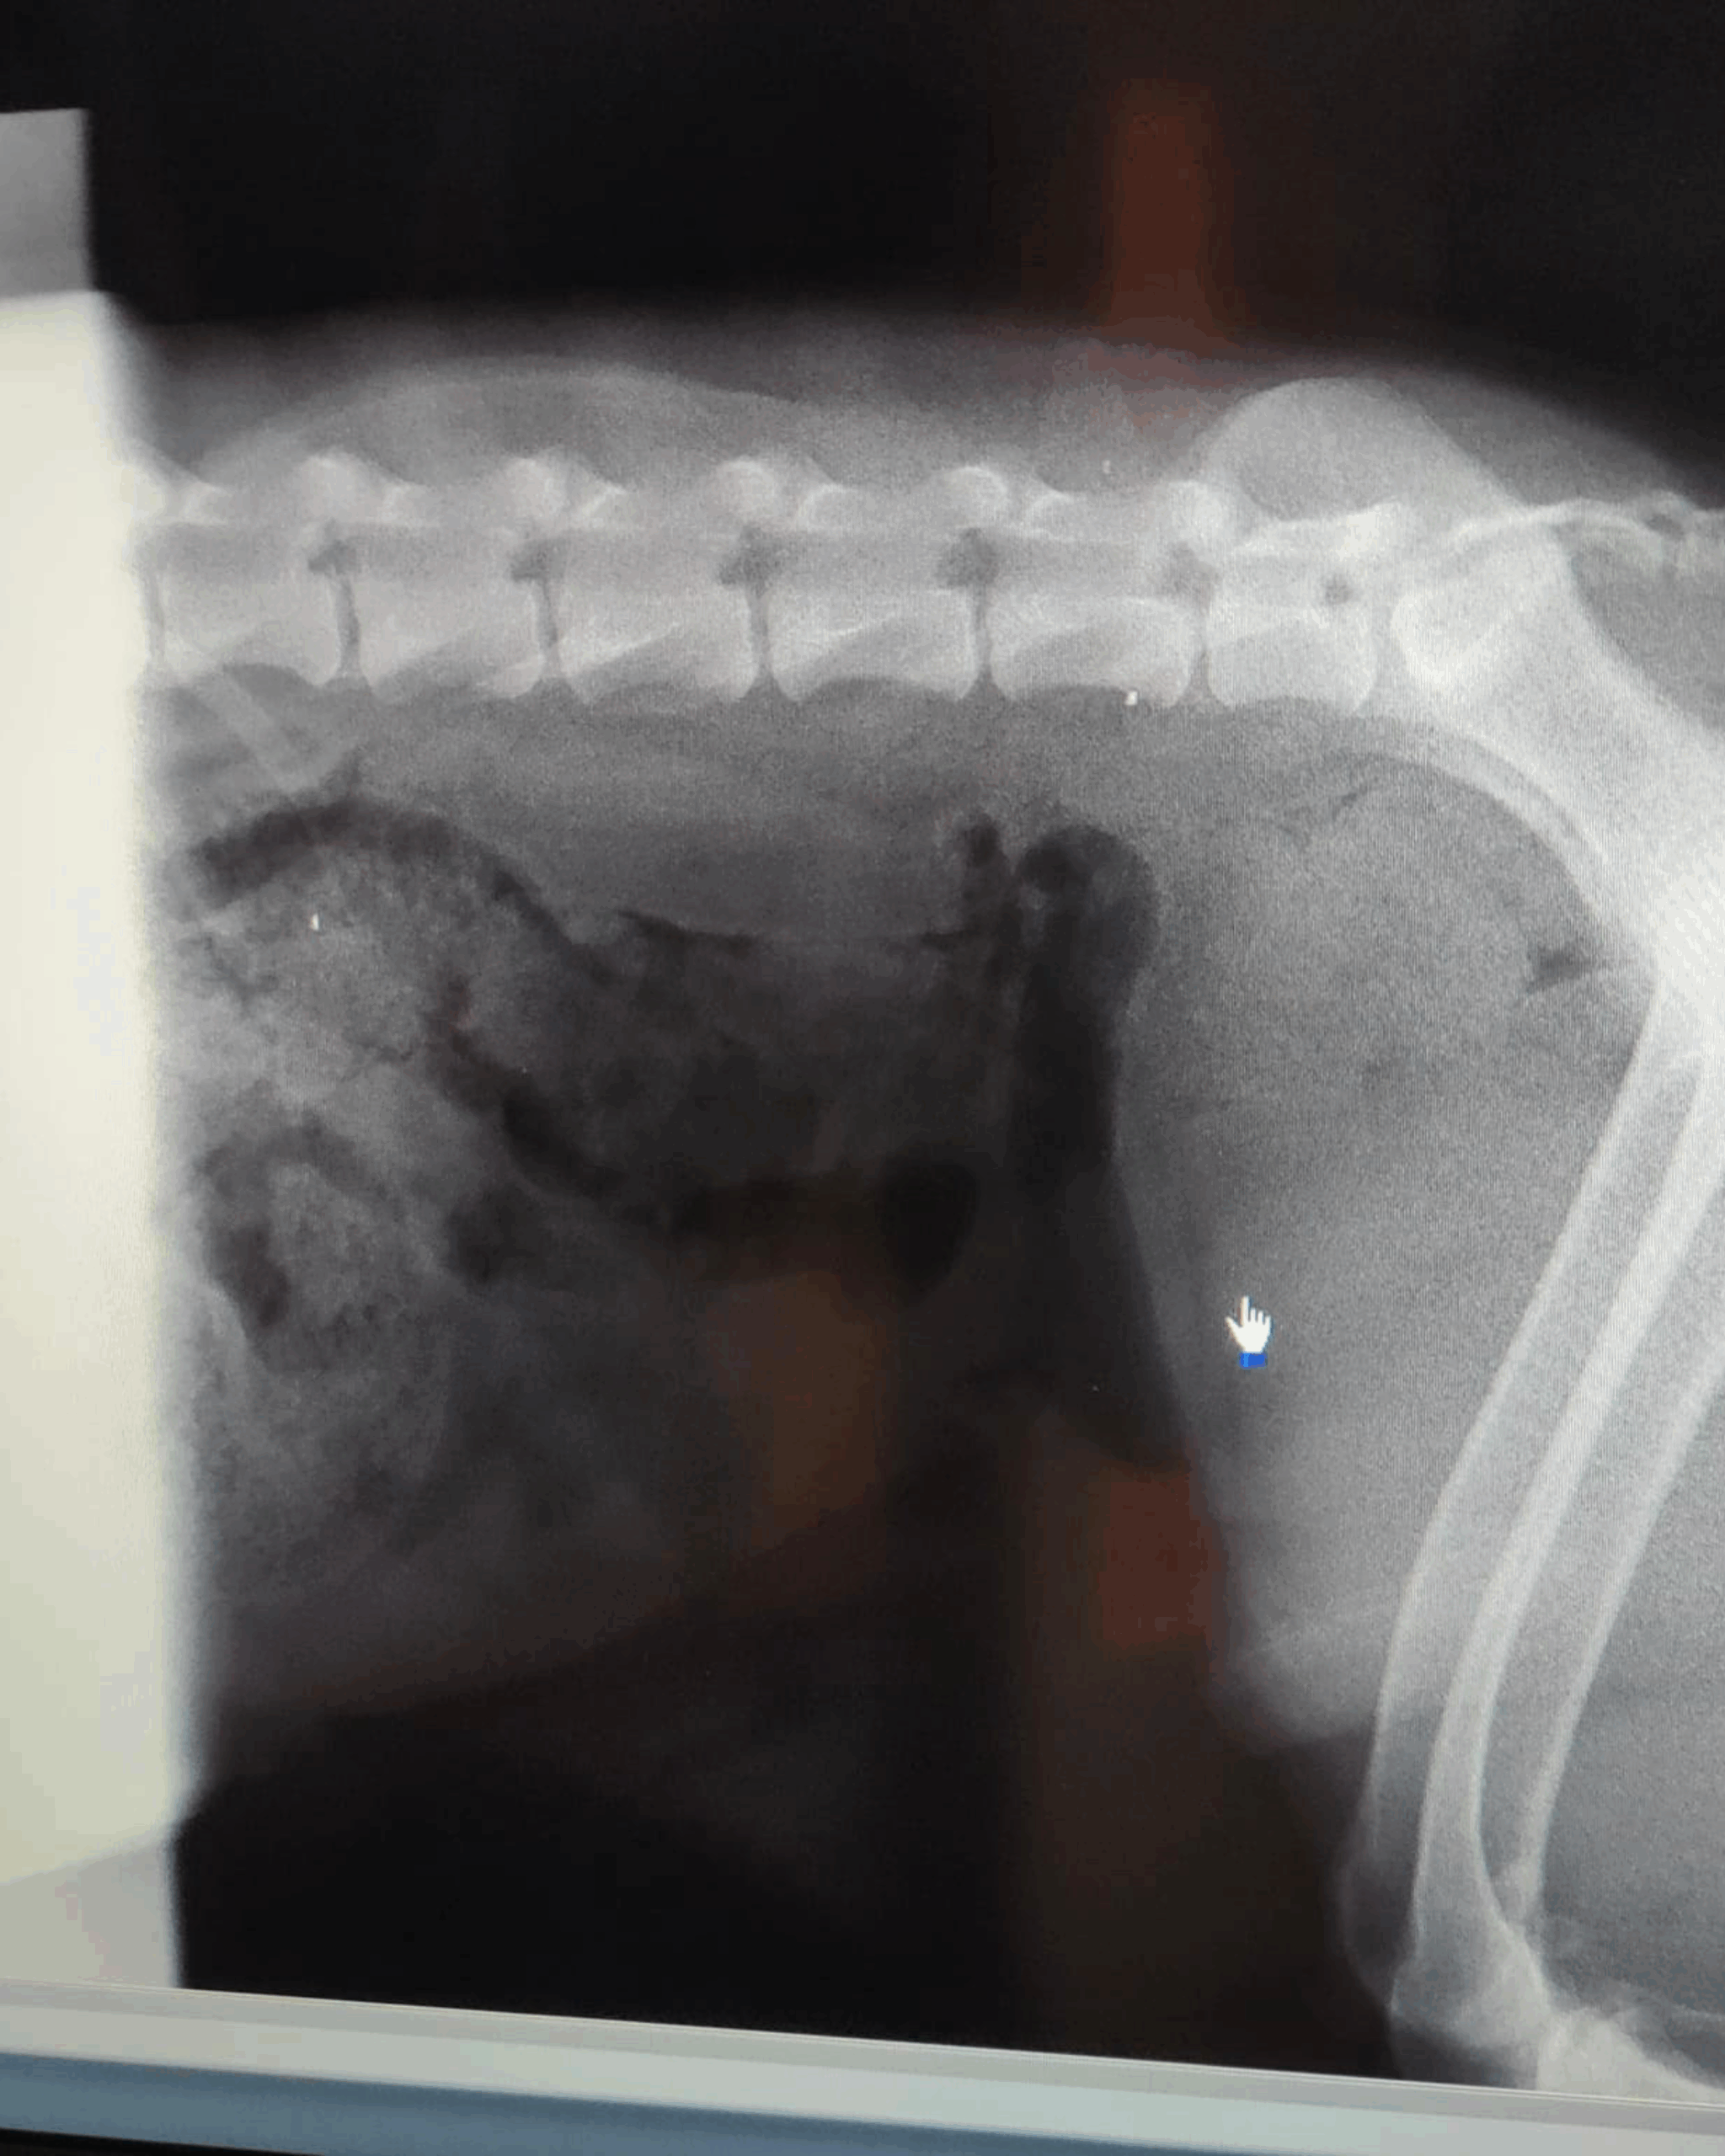

Jego skóra i sierść były w fatalnym stanie. Rany nie chciały się goić – znikały w jednym miejscu, a pojawiały się w kolejnym. W kwietniu 2023 roku, gdy Denver posmutniał i unikał ruchu, wykonaliśmy badanie RTG. Okazało się, że cierpiał na zapalenie mięśni, a dodatkowo ktoś kiedyś strzelał do niego ze śrutu – do dziś ma go w łapce.